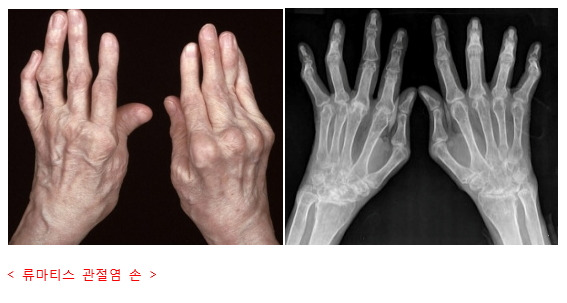

류마티스 관절염은 우리 몸의 면역 체계가 자기 관절을 공격해서 염증이 생기는 자가면역 질환이에요. 초기에는 ‘설마 내가?’ 하고 넘기기 쉬운 미묘한 증상으로 시작되는 경우가 많답니다. 하지만 류마티스 관절염은 초기 증상을 얼마나 빨리 알아차리고 조기 진단받느냐에 따라 예후가 크게 달라져요. 조기 진단은 관절 손상을 최소화하고 건강한 일상을 유지하는 데 핵심적인 역할을 하거든요. 이 글에서는 류마티스 관절염의 초기 증상과 조기 진단의 중요성에 대해 자세히 알려드릴게요.

- 관절 손상 최소화: 시간이 지날수록 관절 변형이 심해져 일상생활에 큰 제약을 초래할 수 있어요. 조기 치료가 이를 막습니다.

- 검사: 혈액 검사 (류마티스 인자, 염증 수치), 영상 검사 (X-ray, 초음파, MRI) 등을 통해 관절 상태를 확인합니다.